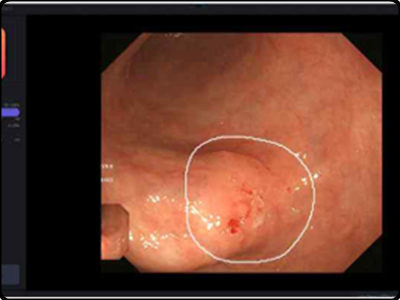

위암의 조기 진단이 힘든 이유 중 하나가 바로 위암의 초기 증상이 배탈이나 속쓰림 같은 보편적인 위장 질환과 증상이 동일하다는 점입니다. 이로 인해서 초기에 발견하지 못하고 치료시기를 놓치는 경우가 있습니다.

위의 암세포 증식은 위기능을 떨어트려 낮아지게 만들어 잦은 배탈 또는 소화불량으로 지속될 수 있다고 합니다. 특히 특출난 이유없이 배탈이나 소화불량이 오랜 시간동안 계속된다면 전문의에게 찾아가 검진을 받아보시는 것이 좋습니다.

조기 위암 환자의 경우 약 80% 가량은 위암 초기증상등의 증상을 느끼지 못했다고 합니다. 아무런 전조증상이 없다가 갑자기 위염인가 싶을 정도의 가벼운 속 쓰림 증세가 나타나게 됩니다. 이렇게 되면 이미 조기진단과 자가진단의 시기를 놓쳐 암을 키우는 경우가 많다고 합니다. 그러니 예방차원에서 정기적인 정기검진은 꼭 필요합니다.